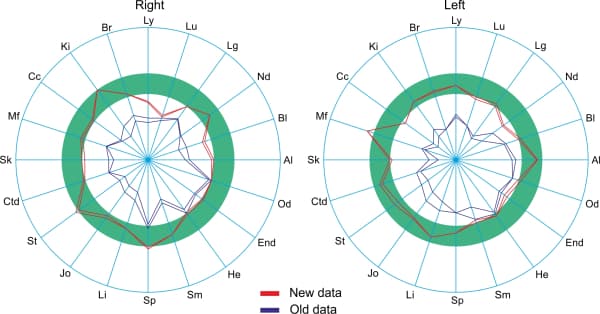

The test subject’s circular charts at the beginning of the workday (before application of the Aires Defender) (Fig. 3) and after working for 6 hours with the Aires Defender (Fig. 4).

Before applying the Aires Defender, a moderate asymmetry of the charts was observed due to the depression of some meridians and the activation of other meridians.

After 6 hours of working under the protection of the Aires Defender, the circular chart became more symmetric and measurements for the majority of the meridians were in the normal range of values (green band).